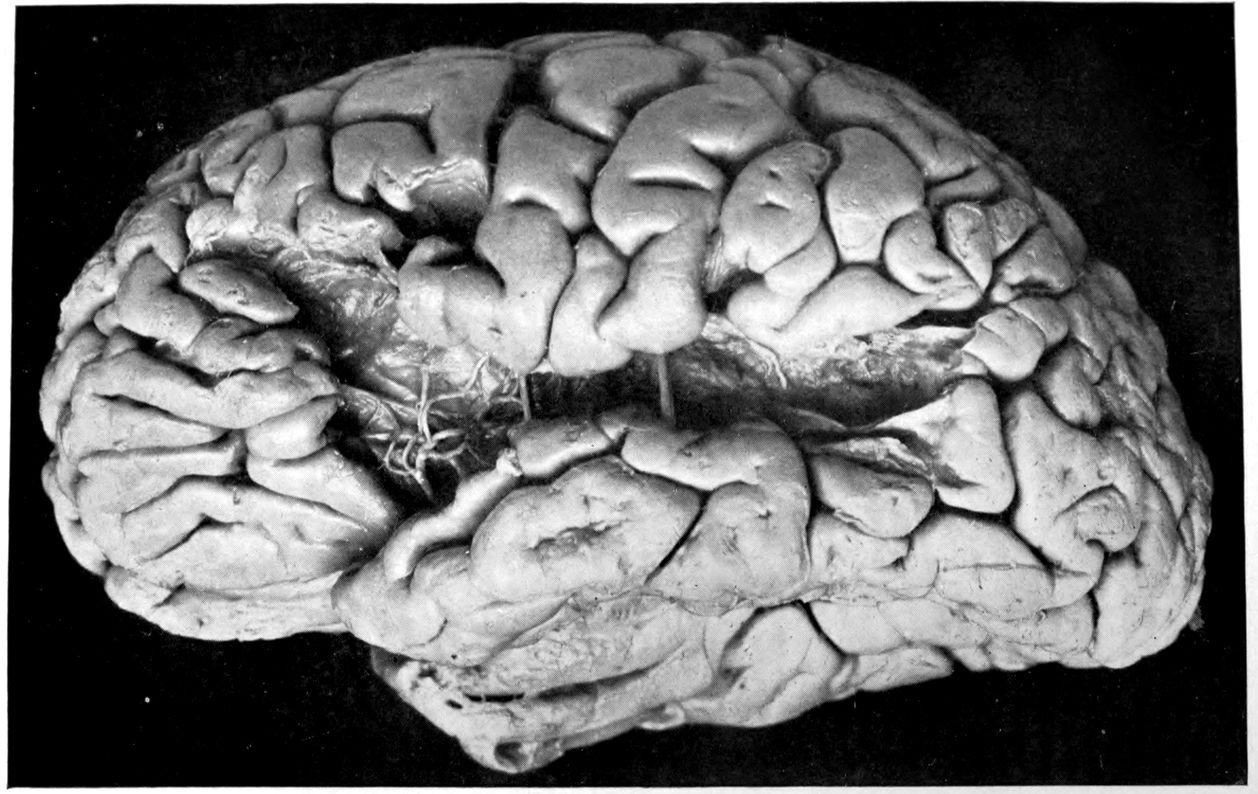

Case 4. James Pierce was an almshouse transfer to the Danvers Hospital in his fiftieth year. He died three years later. The accompanying brain pictures demonstrate so extensive a lesion of the left hemisphere that it is of great interest to determine if possible the genesis and course of his disease. It appears that syphilis had been acquired somewhere about the age of 38 or 40, so that the total duration of the process was between 13 and 15 years. In Pierce’s forty-third or forty-fourth year, he had a shock while walking in the streets of his native city, whereupon he was subsequently transferred to the Danvers Hospital, whose data have been summed up as follows (we are obliged to Dr. Charles T. Ryder for these data):

The autopsy findings were as follows:

Head: Calvarium of moderate thickness; diploë present; dura slightly adherent over bregmatic region. Longitudinal sinus contains cruor clot. Dura is somewhat thickened and slightly more opaque than normal. Pacchionian granulations, small but fairly numerous. Pia contains throughout a considerable excess of clear 44serous fluid. The convolutions in general are of good breadth and proportion. There is an atrophic area roughly circular in outline and about 2 cm. in diameter in the posterior part of the right third frontal convolution corresponding to Broca’s area on the opposite hemisphere. The space thus formed is filled with edema held by the pia. On the left side is a similar subpial collection which covers the site of the posterior portions of all of the third frontal convolutions, parts of the lower end of the precentral convolution, and the whole of the first temporal convolution, which have disappeared entirely. The basal vessels show slight changes.

Cerebellum and basal ganglia are grossly normal.

The spinal membranes are negative. The regions of the pyramidal tracts in the cord are firm, project slightly from surface of section, and are china white.

Summary: Here is a picture made up almost purely of Vascular Neurosyphilis, with Secondary Spinal (Pyramidal Tract) Changes. Doubtless the genesis of this picture is allied to that of Case 1 (Alice Morton) and to that of the terminal vascular complications in a tabetic, Case 2 (Francis Garfield).

The absence of meningeal and parenchymatous (i.e., outside the region of necrosis produced by the vascular disease) lesions is characteristic of an important group of neurosyphilitic diseases. It is clear that the case, although one of extensive lesions, is not one of diffuse lesions in the sense of Case 1 (Alice Morton).

Vascular neurosyphilis—effects of syphilitic thrombosis of Sylvian artery 10 years before death. (Case 4.)

Case 4. (See previous figure for brain lesion.) Three levels of the spinal cord showing unilateral pyramidal tract sclerosis, 10 years after cerebral thrombosis.